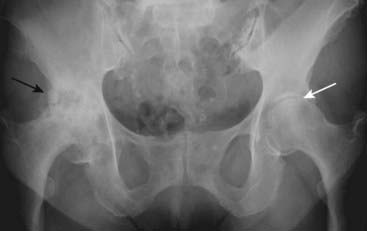

Figure 23-19 Ankylosing spondylitis.

Ankylosing spondylitis is an enthesopathy, a process that produces inflammation with subsequent calcification and ossification at and around the entheses, which are the insertion sites of tendons, ligaments, and joint capsules (solid white arrow points to bony overgrowth at the ischial tuberosity). Bilaterally symmetrical sacroiliitis is the hallmark of ankylosing spondylitis. This eventually leads to bony fusion or ankylosis of the SI joints until they disappear as joints altogether (solid black arrows). The symphysis pubis is also ankylosed (dotted black arrow).